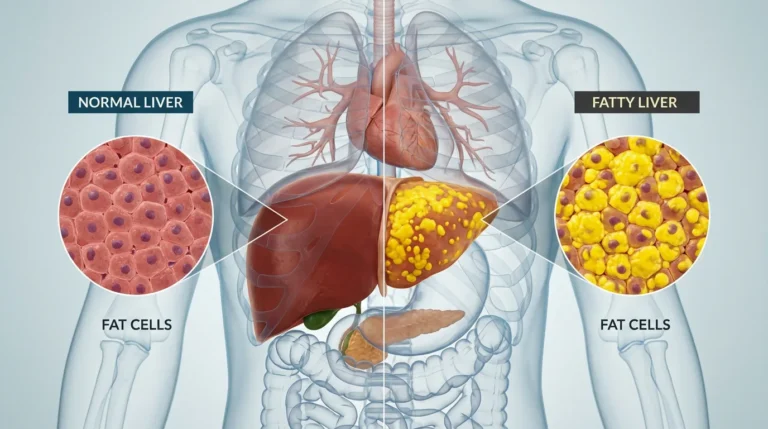

What Is Fatty Liver Disease?

Lorem ipsum dolor sit amet, consectetur adipiscing elit. Ut elit tellus, luctus nec ullamcorper mattis, pulvinar dapibus leo.Fatty liver disease occurs when excess fat builds up in liver cells. It is mainly classified into two types:

- Non-Alcoholic Fatty Liver Disease (NAFLD) – commonly linked to lifestyle factors such as obesity and diabetes

- Alcoholic Fatty Liver Disease – caused by excessive alcohol consumption